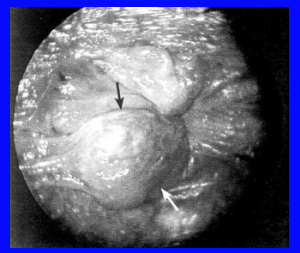

הטחורים החיצוניים נוצרים מהתרחבות המקלעת הוורידית של הטחורים התחתונים (Inferior hemorrhoidal) (תמונה 14.7). הטחורים נוצרים בגובה הכניסה לתעלה האנלית ומכוסים באפיתל רב-שכבתי. העור שמתחת למקלעת הוורידית גדל עקב ההתרחבות הוורידית ופקקת נשנית של הוורידים. גדילה זו של העור יוצרת תגי עור (Skin tags) בכניסה לפי הטבעת.

בדרך כלל, טחורים חיצוניים הם אי-סתמיניים. לעתים עקב פקקת של וריד במקלעת הוורידית בטחור (Thrombosed external hemorrhoids), החולים סובלים מכאבים, מאי-נוחות בפי הטבעת ומתחושת נפיחות או גוש במקום. בבדיקה ניתן לראות טחור בולט בצבע כחול-שחור, רגיש מאוד ובצקתי בכניסה לפי הטבעת (תמונה 15.7). טחורים חיצוניים אינם מדממים, אלא אם כן הם פקקתיים והפקקת הוורידית פוקעת עצמונית.